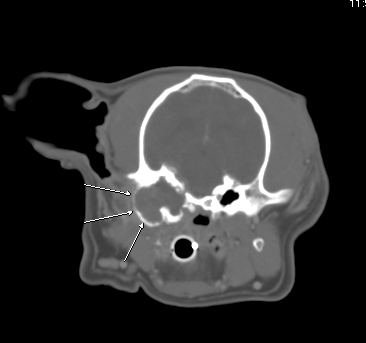

Fig 1:

Transverse CT showing expanded and irregular, tissue filled left tympanic bulla